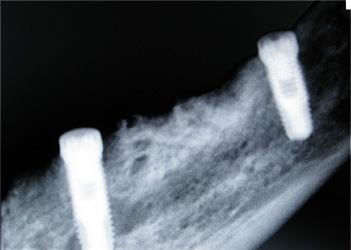

Resultado de colocação de implante dentário na Clínica São Filinto

Caso 8 - Colocação de implantes dentários para reabilitação com prótese fixa em zircónio cerâmica no 4º quadrante.

![]() |